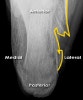

X-ray : Normal calcaneus(Lateral view)

X-ray : 종골 골절(Calcaneal fracture) - Lateral view

1. Flattening of Bohler's angle

2. Depression of the articular surface of the posterior subtalar joint (red line)

from its normal position (green line)

3. Fracture lines can be seen passing through the calcaneus